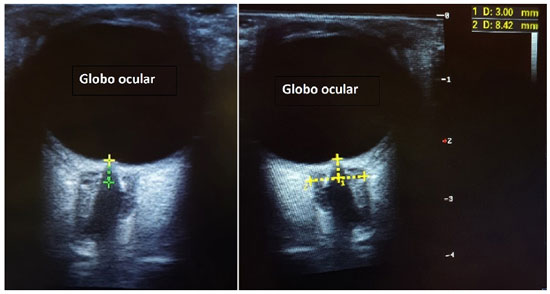

Paciente do sexo masculino, 62 anos, diabético e hipertenso, deu entrada no Departamento de Emergência com queixa de cefaleia súbita e rebaixamento do sensório, 3 horas antes de sua chegada. Seus sinais vitais da entrada mostravam hipertensão com PA 163x110 mmHg, taquicardia com FC 110 bpm, com boa saturação em ar ambiente de 97%, apesar do quadro de rebaixamento e escala de coma de Glasgow de 10 (AO 3 RV 3 RM 4). Poucos minutos após sua chegada, antes mesmo que fosse levado para realizar neuroimagem, paciente apresentou episódio de convulsão tônico-clônica generalizada, ocasião na qual houve piora do rebaixamento. Foi hidantalizado e intubado na sequência. Apesar das medidas para neutroproteção, paciente apresentou instabilidade hemodinâmica, com hipotensão de 92x57 mmHg. Não havendo condições de transporte para realizar neuroimagem, foi realizado ultrassom beira leito da bainha do nervo óptico, que mostrou aumento desta com achado de 8,42 mm de dilatação, corroborando com a hipótese de hipertensão intracraniana que ditava o quadro clínico. Foram iniciadas medidas para aumento da pressão intracraniana, assim como correção da hipotensão, com posterior estabilização hemodinâmica. Realizou, então, neuroimagem, com achado de volumosa hemorragia intraparenquimatosa centrada em núcleos da base à direita, associada a hemoventrículo difuso e sinais de hipertensão intracraniana (Figuras 1 e 2). Foi optado por neurocirurgia manter conduta conservadora do quadro.

Esse estudo pode ser feito beira leito, com um transdutor de alta frequência, tendo como exemplo o probe linear. A estrutura a ser visualizada é a entrada do nervo óptico no globo ocular, com sua respectiva bainha. Devemos então obter uma imagem que mostre a distensão máxima da bainha, com mensuração de seu diâmetro de 3mm posterior ao globo (Figura 3). Feito isso, traçamos uma linha reta usando o diâmetro transversal máximo da bainha, atravessando o ponto final dos 3mm determinados anteriormente (Figura 4).

Nosso paciente em questão apresentou uma dilatação de 8,42 mm da bainha do nervo óptico, como podemos observar na Figura 4 acima.